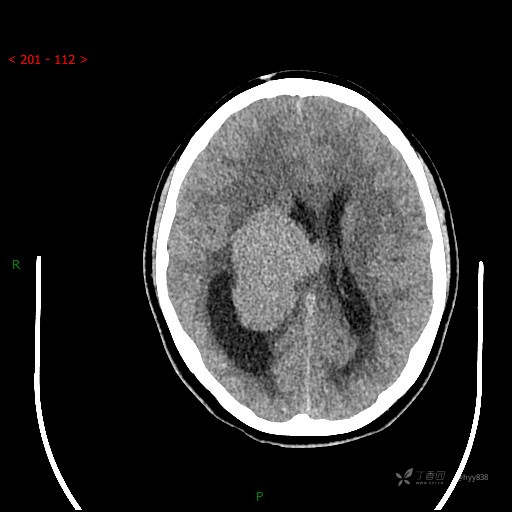

简要病史:患者于1月前无明显诱因出现视物模糊,无明显头痛头晕,无恶心呕吐,无昏迷,无肢体偏瘫等症状,就诊于当地医院头部CT考虑:右侧丘脑、脑室占位。予以对症处置后家属为求进一步诊治来我科,以“颅内占位”收入院。 起病以来,精神、饮食、睡眠欠佳,大小便正常,体力下降,体重无明显变化。

临床诊断:脑室占位

颅脑CT平扫